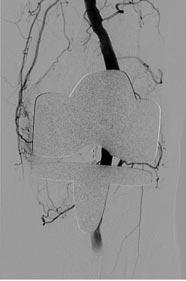

antimicrobiële therapie gestart, te weten amoxicilline en ceftriaxon iv in hoge dosis. De diagnose werd bevestigd door liquordiagnostiek die middels kweek een Klebsiella pneumoniae als verwekker aantoonde. Middels whole genome sequencing (WGS) bij het RIVM werd vastgesteld dat het om MLST type 23 ging welke bekend staat als de ‘hypervirulente Klebsiella pneumoniae (hvKp). Deze was gevoelig voor alle geteste antibiotica, met uitzondering van amoxicilline (resistent). Uit aanvullend onderzoek met MRI-cerebrum bleek er sprake te zijn van multipele cerebrale abcessen (figuur 1 en 2). Bijkomend op PET-CT werden pulmonale abcessen, een leverabces en sterk verhoogde activiteit in de prostaat gezien. Echografisch werd een abces van de prostaat uitgesloten. Het leverabces kon niet volledig worden gedraineerd, maar de kweek het punctaat toonde dezelfde verwekker. Een cardiale strooihaard werd middels een echo cor uitgesloten. Mogelijk is een prostatitis de primaire infectiebron van K. pneumoniae geweest.

Figuur 1.

3DT1 HR gradiënt sequentie na intraveneuze toediening van gadolinium toont een tweetal ringvormig contrast aankleurende lesies met centrale non-enhancement van respectievelijk 1,4 cm links frontaal en 1,0 cm links occipitaal. Let ook op de aankleuring langs het ventrikelependym links occipitaal.

Figuur 2.

DWI sequentie B1000 toont uitgesproken diffusierestrictie in de respectievelijke laesies links frontaal en links occipitaal als ook in de zijventrikel-occipitaalhoorn links. Dit bevestigt de diagnose hersenabcessen met daarnaast meningitis/ventriculitis in de linker zijventrikel.

een later stadium is, wegens koorts en progressie van zowel aantal als grootte van hersenabcessen op MRI-cerebrum, co-trimoxazol 2dd960mg tijdelijk toegevoegd tot kliniek en infectiewaarden verbetering toonden. Klinisch knapte de patiënt goed op en volgde poliklinisch een uitgebreid revalidatie-traject. Er bleef sprake van milde cognitieve stoornissen en doofheid van het linkeroor na de doorgemaakte meningitis, maar buiten dat was er sprake van nagenoeg volledig herstel.

Voor de diagnostiek naar cerebrale abcessen is een MRI met diffusie en post-gadolinium opnames essentieel. De laesies vertonen diffusierestrictie, dat wil zeggen een hoog signaal op de DWIopnames met corresponderend laag signaal op de ADC-opnames. Diffusierestrictie is indicatief voor pus. Watermoleculen kunnen in het ingedikte materiaal (pus) niet vrij diffunderen over semipermeabele barrières van bijvoorbeeld extracellulair naar intracellulair, maar blijven binnen het verdikte abceskapsel. Na gadolinium wordt er (scherpbegrensde) randaankleuring gezien van alle cerebrale abcessen.